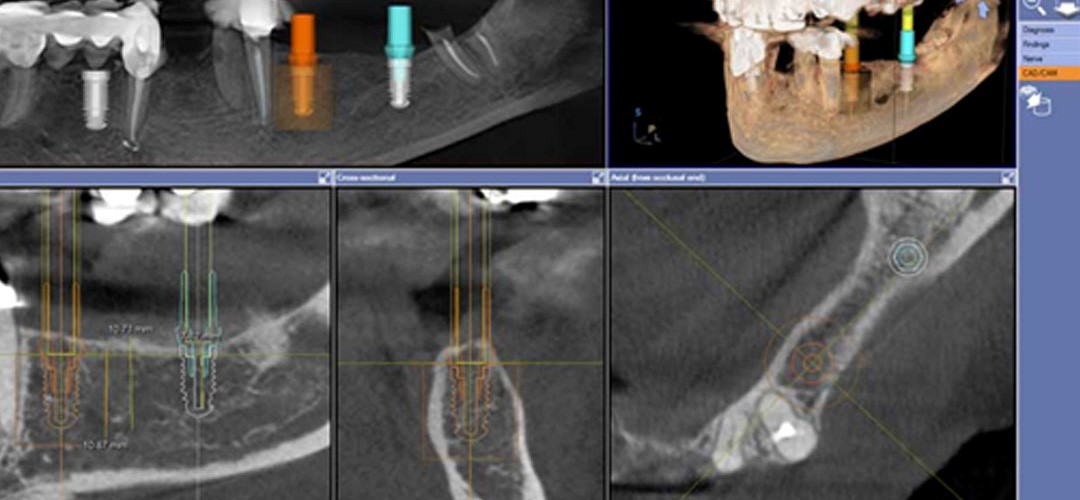

1. Phục vụ cho cấy ghép Implant:

CBCT trong việc lập kế hoạch điều trị Implant sử dụng hình ảnh 3D và đa lớp cắt để xác định chính xác chiều cao, độ rộng và giải phẫu của phần xương hàm và xương ổ răng cũng như mối tương quan vùng mất răng với cấu trúc giải phẫu liền kề như ống thần kinh răng dưới. Đặt Implant với máng hướng dẫn phẫu thuật có thể được thực hiện với các dữ liệu CBCT. Với khả năng 3 chiều của CBCT, các nhà lâm sàng có thể quyết định liệu có cần đến việc ghép xương, nâng xoang trước khi đặt Implant hay không cũng như chọn kích thước implant phù hợp nhất cho từng vùng xương.

Lập kế hoạch đặt implant ảo trên phim CBCT